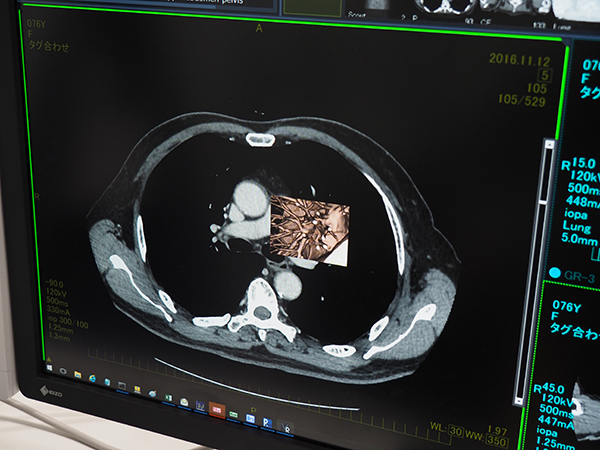

HOPE LifeMark-PACSは,横河医療ソリューションズと共同開発されたPACSで,専業ベンダーの開発による画像保管,表示,レポーティングの高い機能と,富士通が得意とする電子カルテとの密な連携機能によって,快適な読影環境を提供する。ビューワやレポート作成画面からワンクリックでカルテが起動できる。ビューワ機能としては,画像自体の類似度で同一スライスを判断して自動位置合わせを行う“画像認識位置合わせ”や,トモシンセシスにも対応するマンモグラフィ機能を標準搭載する。また,富士通独自の機能として,ビューワ上で見たい領域だけを画面を切り替えずに3D化する“ROI VR”を搭載している。関心領域を矩形で選択し,右クリックメニューからROI VRを選択することで,矩形内にVR画像が作成される。肺野や骨といった条件の変更も可能で,読影補助や患者説明に利用できる。

関心領域だけを選択して3D化する“ROI VR”